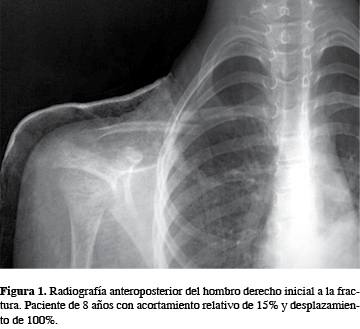

Acortamiento Relativo De Clavicula En Fracturas Pediatricas Su Importancia En La Decision Del Tratamiento Conservador